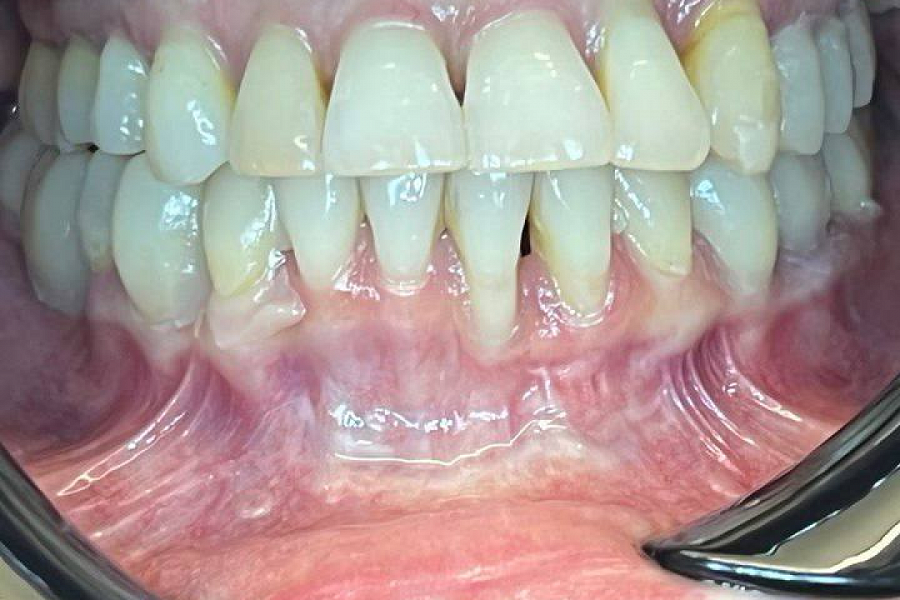

Пациентка обратилась к нам после неудачного ортодонтического лечения в другой клинике, из-за которого появился целый набор проблем:

• челюсть встала в неправильную позицию, что привело к дисфункции ВНЧС и перенапряжению лицевых и жевательных мышц

• начал болеть сустав,

• появился дискомфорт при жевании,

• отдельные зубы стали очень подвижны,

• часть зубов подверглась перегрузке.

Все проблемы решили грамотным тотальным протезированием. Челюсть приняла правильное положение, ушла боль и дискомфорт, а вместе с ними и страх.

В планах операция по устранении рецессии на нижнем резце.